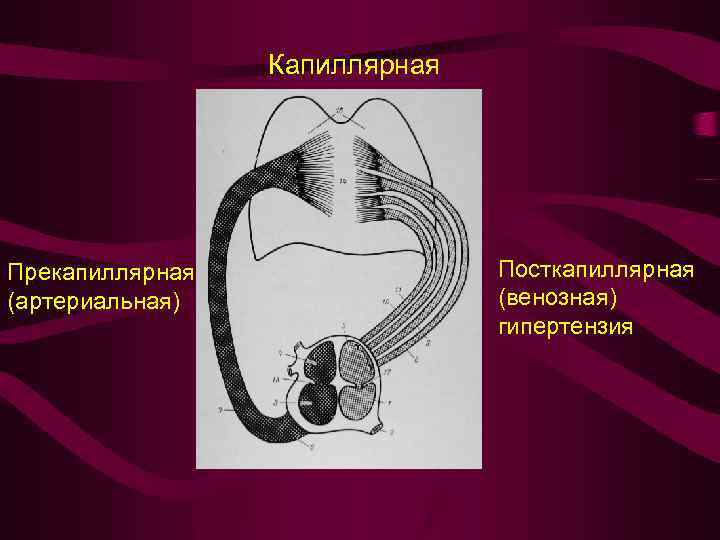

Механизмы перераспределения легочного кровотока Легочная гипертензия обусловлена двумя факторами: объемом кровотока, поступающего в легкое, и сопротивлением ему В зависимости от локализации сопротивления кровотоку различают: прекапилярную капиллярную посткапиллярную гипертензию малого круга.

Механизмы перераспределения легочного кровотока Легочная гипертензия обусловлена двумя факторами: объемом кровотока, поступающего в легкое, и сопротивлением ему В зависимости от локализации сопротивления кровотоку различают: прекапилярную капиллярную посткапиллярную гипертензию малого круга.

Капиллярная Прекапиллярная (артериальная) Посткапиллярная (венозная) гипертензия

Капиллярная Прекапиллярная (артериальная) Посткапиллярная (венозная) гипертензия